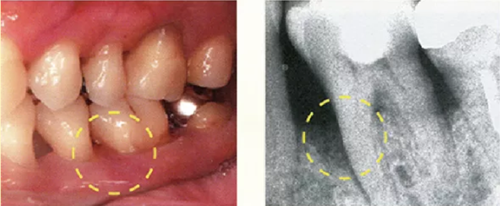

牙周探診在掌握眼睛看不到的部分的狀態(tài)方面,是非常重要的一個檢查。參考X片進(jìn)行探診,可以立體掌握該檢查部位。

然而X片中無法看到所有信息。魚食,牙周探針的工作尖需要像步行一樣在袋底走動運用步行式探診法可以更準(zhǔn)確掌握該部位的狀況。

● 僅有X片,無法掌握到牙周袋底的狀況嗎

因此,在檢測牙周袋深度時,通過 X 片確定牙槽骨的狀態(tài)、根的形態(tài)、牙結(jié)石的附著狀態(tài)等,在腦中有一個大致的印象,應(yīng)該可以很大程度上減少漏檢。

僅通過口腔視診是無法看出何處有骨吸收的。通過拍攝的牙片,可以一定程度上掌握牙槽骨吸收的情況。

如果觀察X片后預(yù)想的狀態(tài)和牙周探診分析出的狀況有很大差異,就需要再次注意此部位并重新做一次牙周探診。